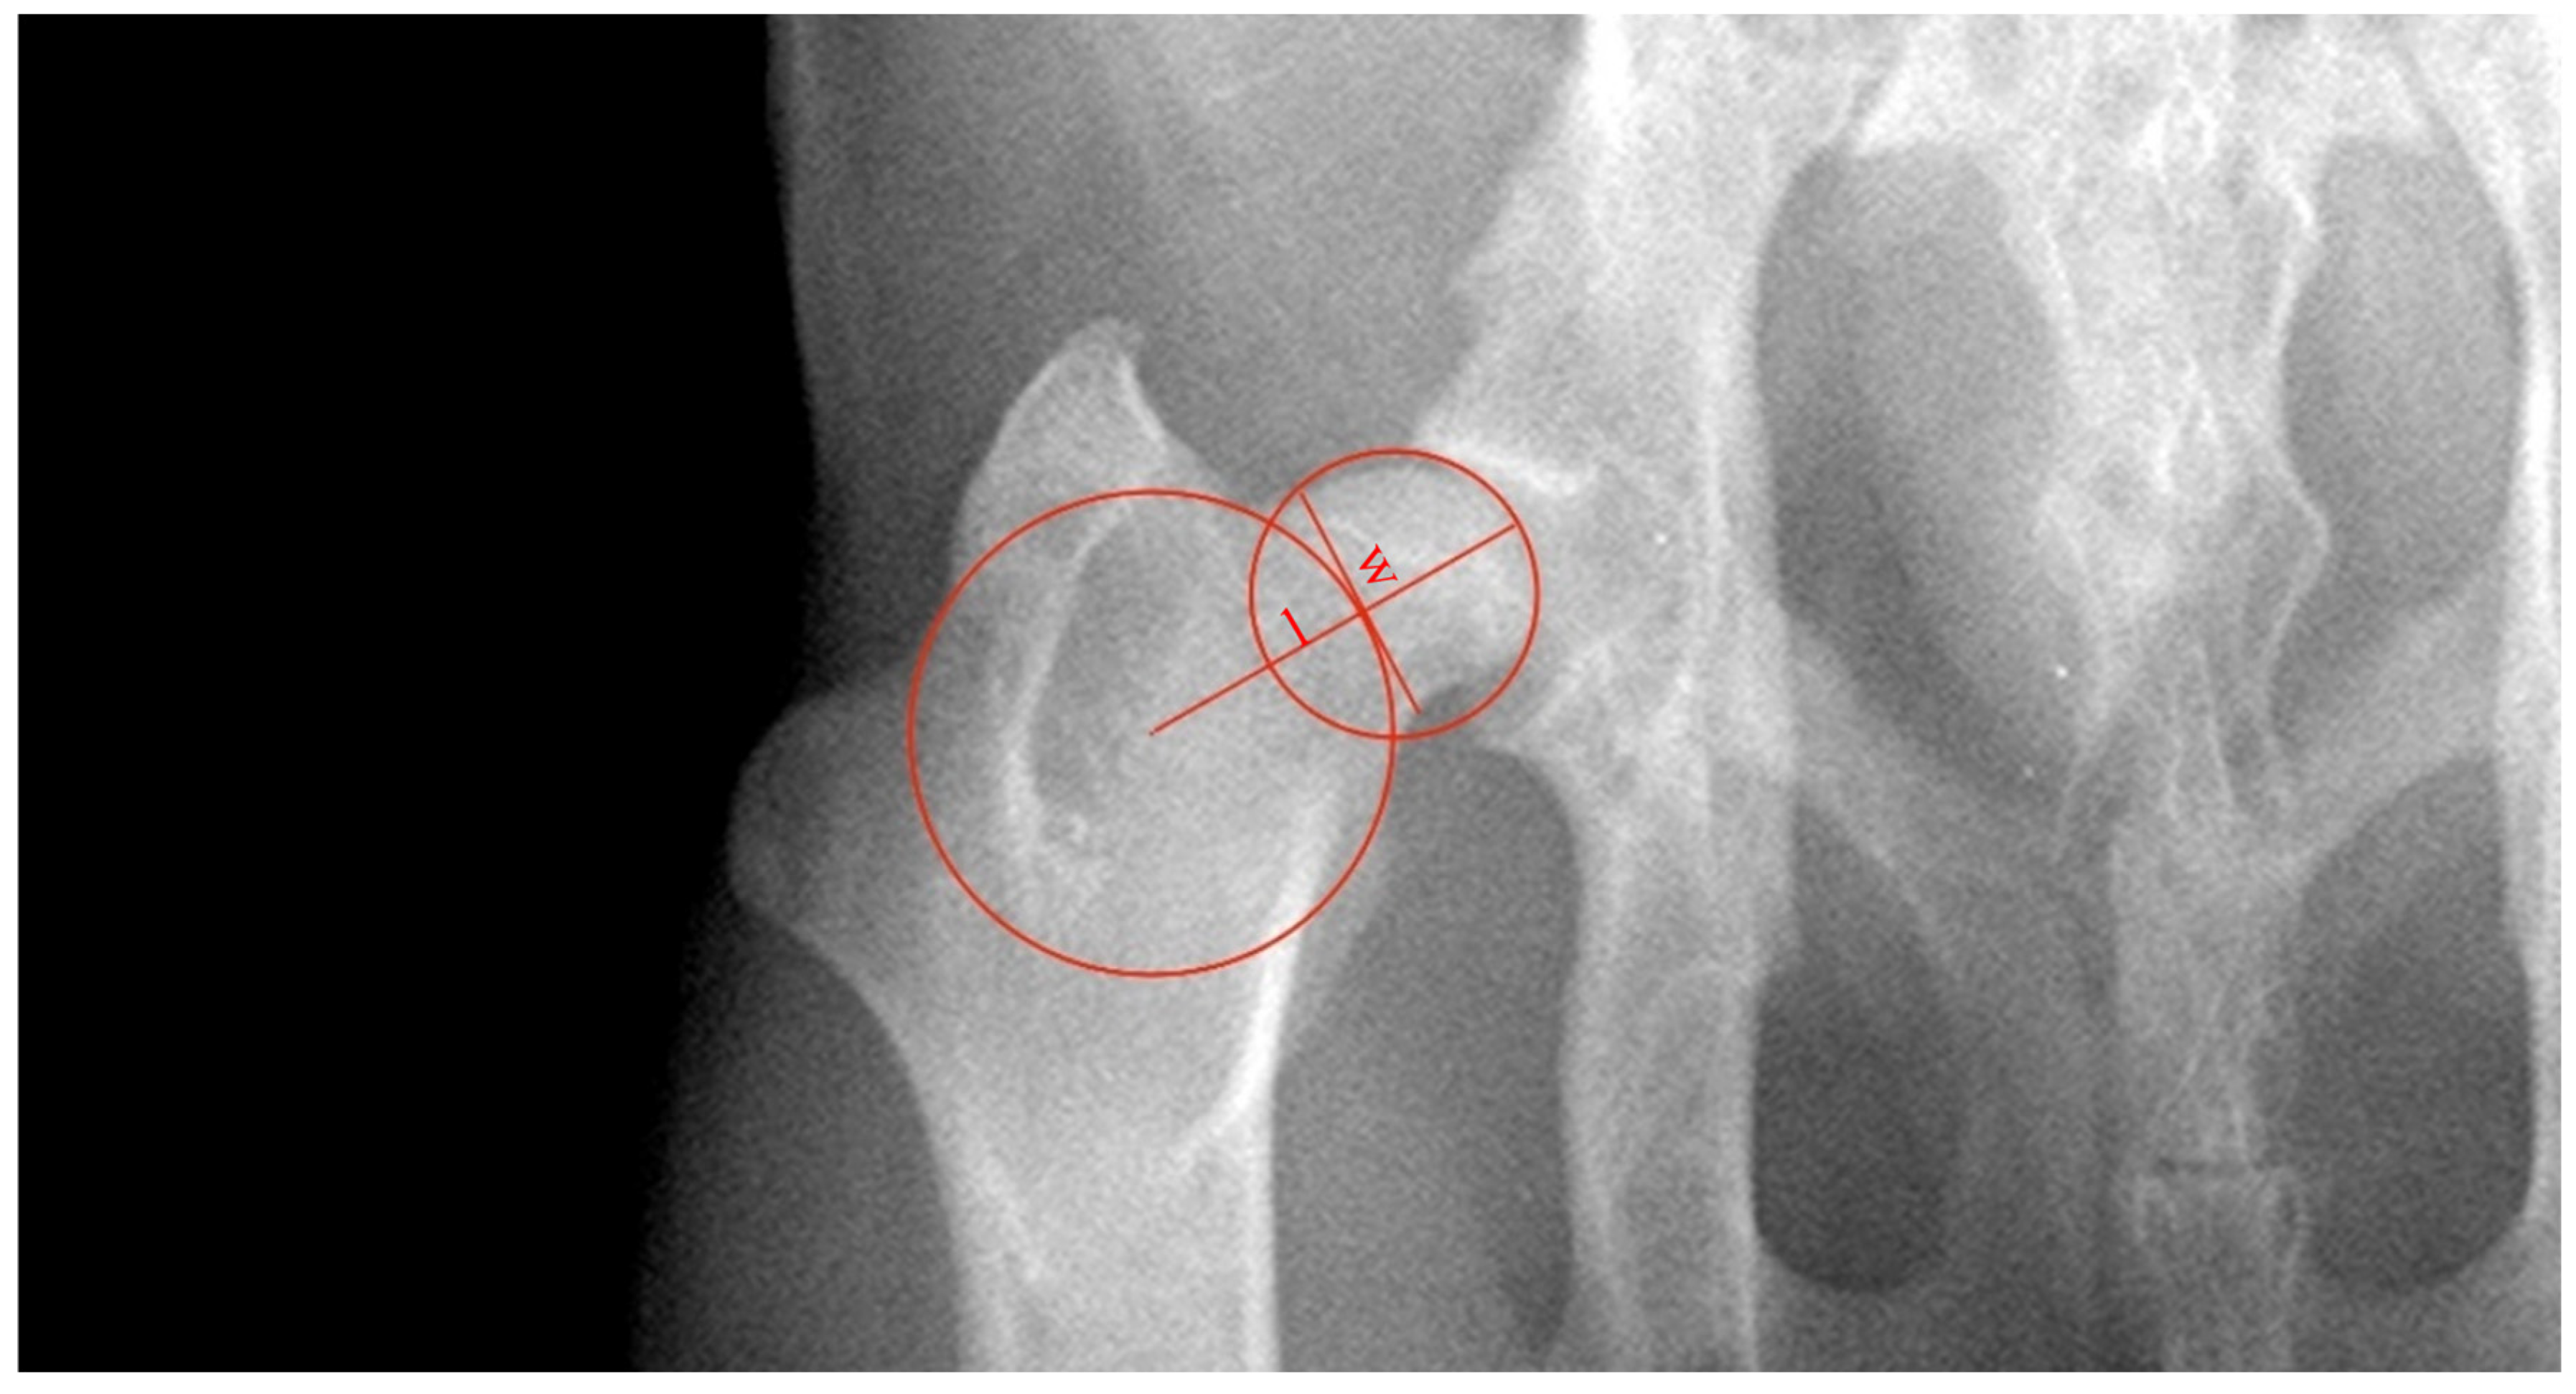

FNLi is defined as the ratio of the length of the neck of the femur (distance ‘l’) and the diameter of the head of the femur (l/Ø, in mm) (Figure 2) [12]. The length of the neck of the femur was defined as the distance between the outer limit of the best-fit circumference drawn in the head of the femur and the center of the best-fit circumference drawn between the greater and third trochanters. The FNWi was measured as the ratio between ‘w’, the width of the neck of the femur, and the distance ‘l’ (w/l, in mm). Distance ‘w’ was established as a line perpendicular to ‘l’ and at the narrowest distance of the neck of the femur tangent to the outer limit of the best-fit the circumference between the greater and third trochanters [13].

Figure 2. Illustration of the methodology used to assess the length index of the neck of the femur (FNLi) and femoral neck width index (FNWi) in a ventrodorsal radiograph of the hip joint. FNLi is calculated as the ratio of ‘l’, the length of the neck of the femur, and the diameter of the head of the femur. The distance ‘l’ was defined as the length between the outer limit of the circumference drawn in the head of the femur and the circumference’s center drawn between the greater and third trochanters. The FNWi was measured as the ratio between ‘w’, the width of the neck of the femur, and the distance ‘l’. Distance ‘w’ was established as a line perpendicular to ‘l’ and at the narrowest distance of the neck of the femur tangent to the outer limit of the circumference between the greater and third trochanters.